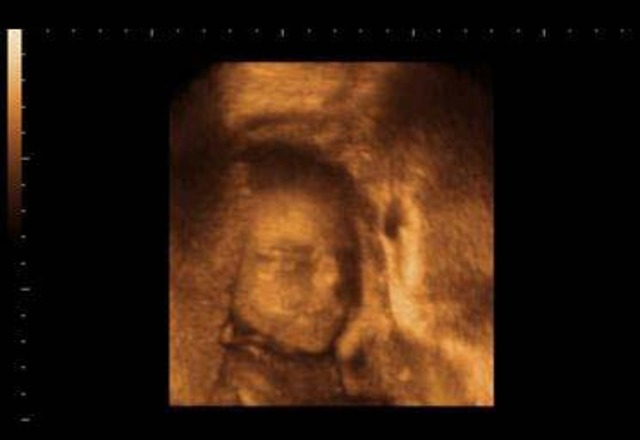

6 Weeks

The heartbeat of the baby is able to be seen with an ultrasound. The nose, mouth and ears are begginning to form. The baby is considered to be a embryo. At this stage you cannot feel your baby kicking. Your baby will start kicking when your at at week 16 through week 24. The baby cannot hear you yet even though the ears are developing. The baby can hear you singing or talking when you are 16 weeks pregnant.